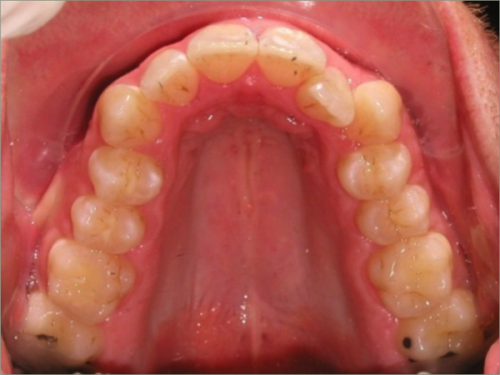

30 year old male:

Diagnosis:

- Upper and lower crowding

- Narrow upper & lowerarch forms

- Open bite

Treatment:

- Invisalign

- Non-Extraction

- 27 months